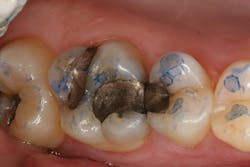

The clinical case in Figure 3 illustrates a patient who presented with a large, failing restoration containing cracks and decay. The patient was interested in an all-ceramic restoration. Occlusion was checked with articulating paper prior to treatment with a CAD/CAM restoration (figure 4). All previous restorative materials were removed from the tooth (figure 5). The tooth was restored using Grandio Core Dual Cure (Voco) build-up material (figure 6). A crown preparation was completed for a chairside CAD/CAM crown using the CEREC system (Dentsply-Sirona). The material of choice for this restoration was IPS e.max CAD (Ivoclar Vivadent), which is seen in Figure 7 after milling and in precrystallization form. The restoration was tried in and then polished, glazed, and placed in the oven for crystallization. The internal surface was then etched with 4.9% hydrofluoric acid, rinsed, and then coated with a silane coupler to create an optimal surface for bonding with the resin luting agent. The tooth was isolated and cleaned prior to etching. Once etched, the adhesive bonding agent (Futurabond U) was activated to mix the two liquids within the single-dose blister package. The blister seal was broken with the bonding agent brush and the adhesive was applied and agitated for 20 seconds. The adhesive was lightly dried for five seconds and then cured with an LED curing light for 10 seconds. A dual-cured adhesive resin luting agent (Bifix QM) was dispensed into the crown with its automix syringe (figure 8). The crown was seated and excess cement was removed after a two-second light cure. The tooth was then flossed and occlusion was checked (figure 9). The patient was very satisfied with the final result.

Figure 3: A large, failing restoration containing cracks and decay